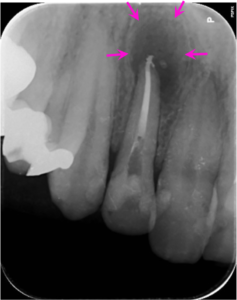

治療中

初診より3回目の治療の後、歯の根の中を清掃し終わった後に内部に薬(MTA)を詰めた直後のレントゲン写真です。

薬は根の中に緊密に詰まっています。一部先から漏れている部分もありますが、のちに吸収されていきます。この時点で初診時と比べて骨が吸収されている部分の境界がぼやけて範囲が小さくなり、改善している兆候がみられます。